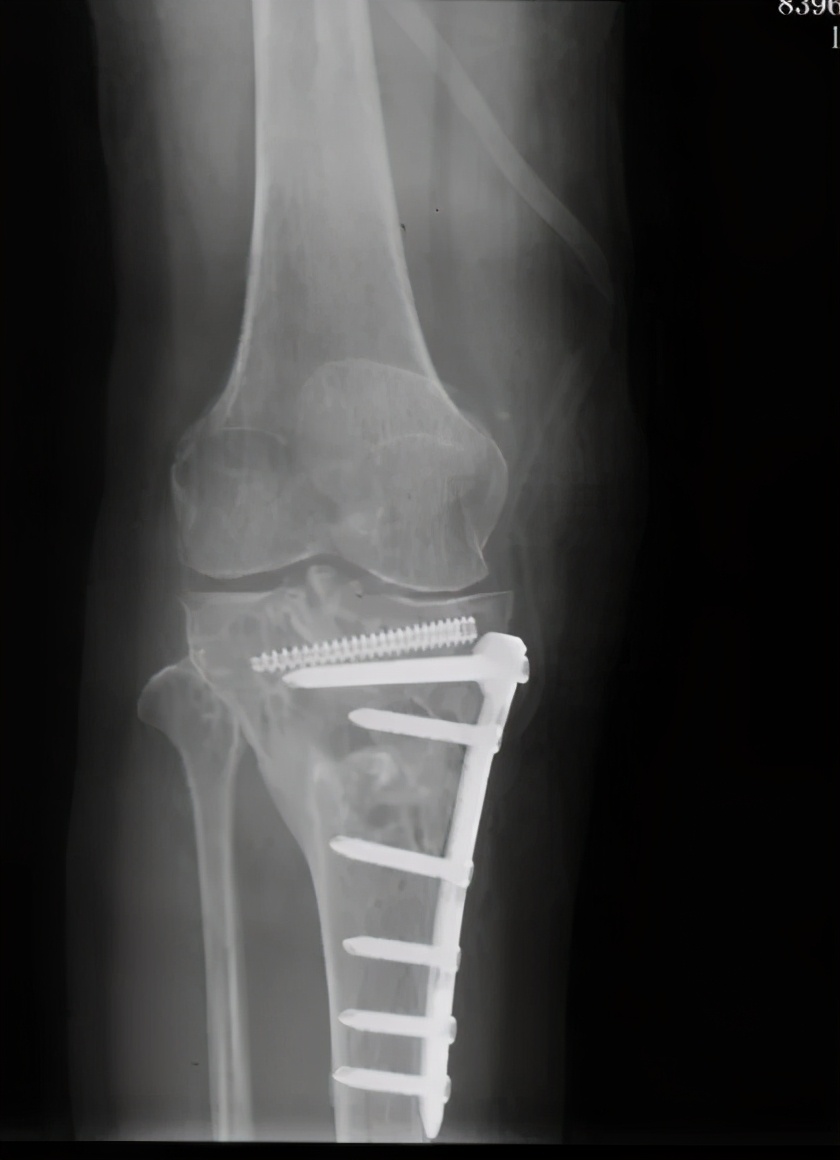

经过详细问诊以及X线检查,发现杨女士胫骨平台畸形愈合,平台大于股骨远端,膝关节对合不佳。刘万军主任决定行胫骨内侧髁截骨(TCVO),经过一系列周密的术前计划,刘主任为杨女士术前量身制作截骨模板,术后杨女士当天便可以下床活动,第二天就可以出院了,看见自己的腿由弯变直,杨女士的脸上露出了久违的笑容,对刘万军主任团队高超的医术赞不绝口。

术后

胫骨内侧髁截骨(TCVO)是一种胫骨高位截骨的方法,从胫骨内侧近端到胫骨髁间嵴(L型截骨),将内翻力线改变为外翻力线,治疗伴有膝关节向外侧半脱位的重度内侧间室骨关节炎的患者。

TCVO不仅可以矫正下肢力线,也能恢复关节面宽度,改善关节稳定性。减少外侧关节半脱位,负重重新分配到外侧间室,调整外侧间室间隙,改善关节内外翻的不稳性。

总之,胫骨高位截骨术是一个微创手术,仅在骨头上切开一道缝隙,再把截骨面以合适的角度撑开,并用接骨板固定,因此不会有骨头的移除,对于伴有膝内翻畸形的膝关节内侧关节面磨损患者是很好的手术选择。